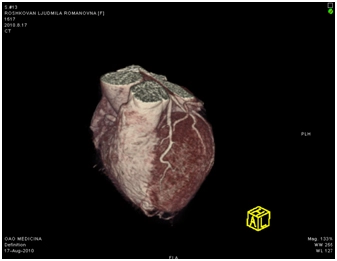

МСКТ коронарных артерий от 08.2010

Ствол ЛКА широкий, имеет ровные контуры, не стенозирован. ПНА в проксимальном сегмента имеет неровные контуры за счет кальцинированных и частично кальцинированных бляшек, просвет артерии на этом уровне сужен до 30-50%, в среднем сегменте определяется ряд пристеночных и циркулярных мягких бляшек, со стенозом артерии до 60-75%, дистальные отделы артерии малого калибра, плохо заполняются контрастным веществом. ОА нормального диаметра, заполняется контрастным веществом без признаков гемодинамически значимого стеноза. ПКА нормального диаметра, в проксимальном сегменте имеются смешанные частично кальцинированные бляшки, стенозирующие просвет до 30%, в среднем сегменте визуализируется пристеночная смешанная бляшка, стенозирующая просвет до 50-70%, дистальный сегмент не изменен. Правый тип коронарного кровоснабжения.

Трехмерная реконструкция